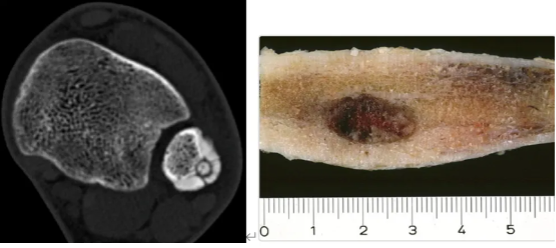

骨样骨瘤是一种孤立性的成骨性肿瘤,为第三大常见的良性骨肿瘤,仅次于内生软骨瘤及非骨化性纤维瘤。好发于5-30岁的儿童与青年(男女比例3:1),通常发生在长骨的骨皮质中。使用CT以及核素骨扫描是骨样骨瘤诊断的主要手段。